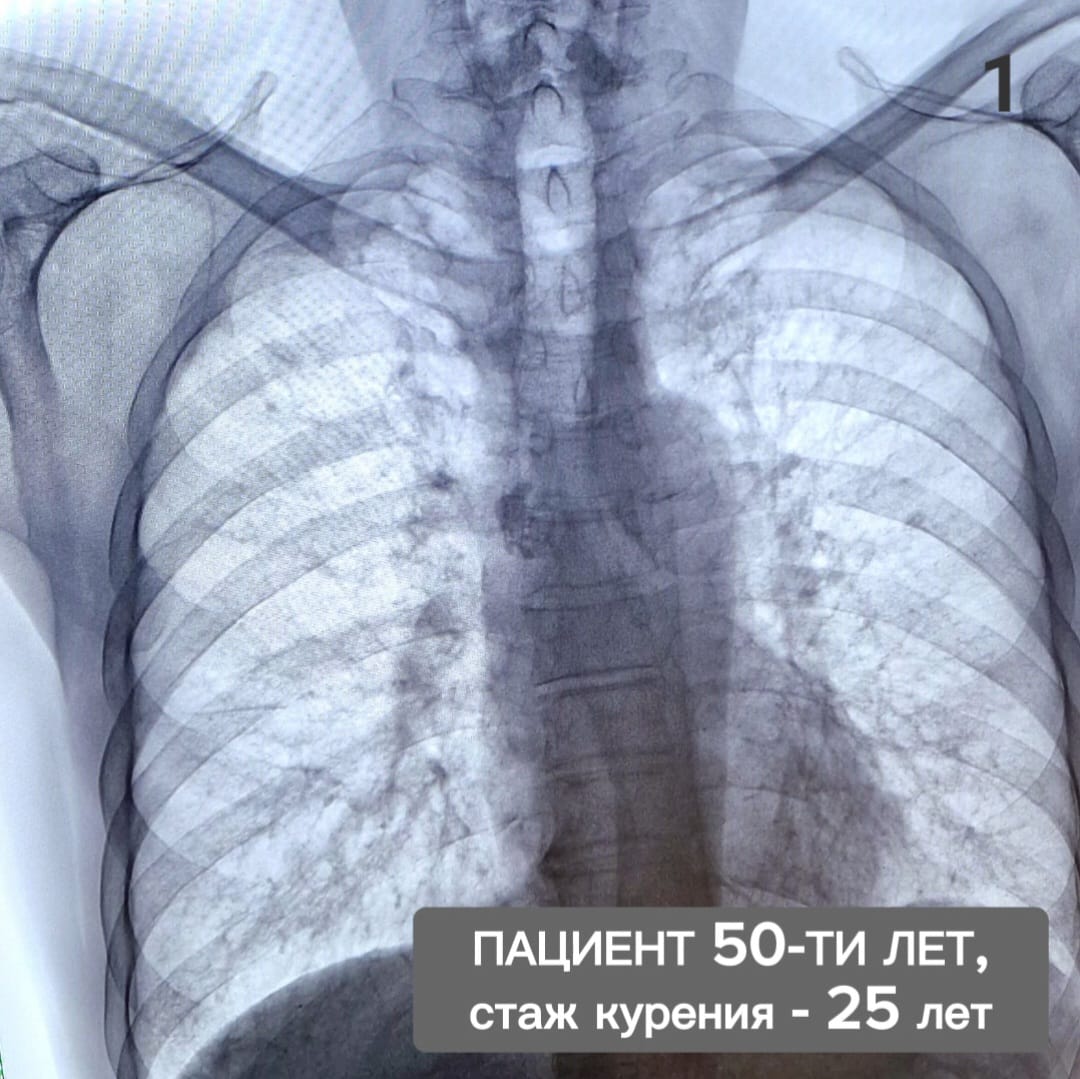

Врачи напоминают: не бывает безопасного курения. Вред от обычных или электронных сигарет, вейпа или кальяна одинаков: курильщики в любом случае потребляют отравляющие и канцерогенные вещества. Представляем два снимка: на одном - лёгкие курильщика с 25-летним стажем, на втором – мужчины, который курил 15 лет, а потом бросил.

«Ренгенографию прошли мужчины-ровесники. Им по 50 лет. Первый не может, не задыхаясь, подняться на 3 этаж, второй – уже 5 лет ходит в пешие походы по самым живописным уголкам страны, - рассказал врач-рентгенолог поликлиники №5 Челнов Рамзиль Гильметдинов. – Один пациент отказался от вредной привычки и теперь дышит полной грудью, другой - страдает хроническим бронхитом, пневмосклерозом, одышкой, имеет нарушение сердечного ритма».